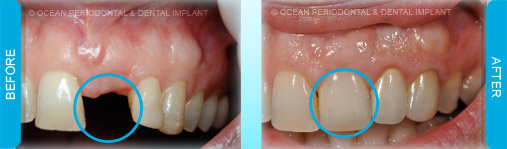

Dental implants are commonly used to replace missing or lost teeth in order to ensure patient comfort, function, and aesthetics. Indeed, there are many treatment options for management of missing teeth, such as bridges, and partial/complete dentures.

Nonetheless, numerous studies have demonstrated that implant-supported restorations are generally deemed to have superior functional and aesthetic outcomes. Furthermore, there are cases where dental implants may be the only logical choice for the restoration of function and aesthetics.